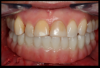

Figure 3 shows a ti-base connection, narrow emergence profile of the zirconia abutment (pink characterization), and final abutment with margins that were computer-generated and computer-manufactured to reflect the appropriate soft-tissue architecture for the patient. As shown in Figure 4, the abutment was seated and torqued to 25 Nm, allowed to rest for 10 minutes, and torqued once again to 25 Nm. The crown was tried in, fit was verified, and occlusion was established. This particular patient was concerned that the implant crown and implant would not look natural. Before beginning the single-tooth replacement with implant dentistry, a diagnostic wax-up and photographic imaging were employed to help develop a natural-looking provisional during the osseointegration phase. A treatment plan was developed and presented to the patient for considering cosmetic dentistry for tooth Nos. 6 through 11. The patient was still apprehensive and chose to begin therapy for only tooth No. 8. Since the final seat date, the patient has been very satisfied with the results of the single-tooth therapy and has committed to completing the cosmetic dentistry services for tooth Nos. 6 through 11.

Fig 4. Seated abutment (left) and crown try-in (right).

Figure 4